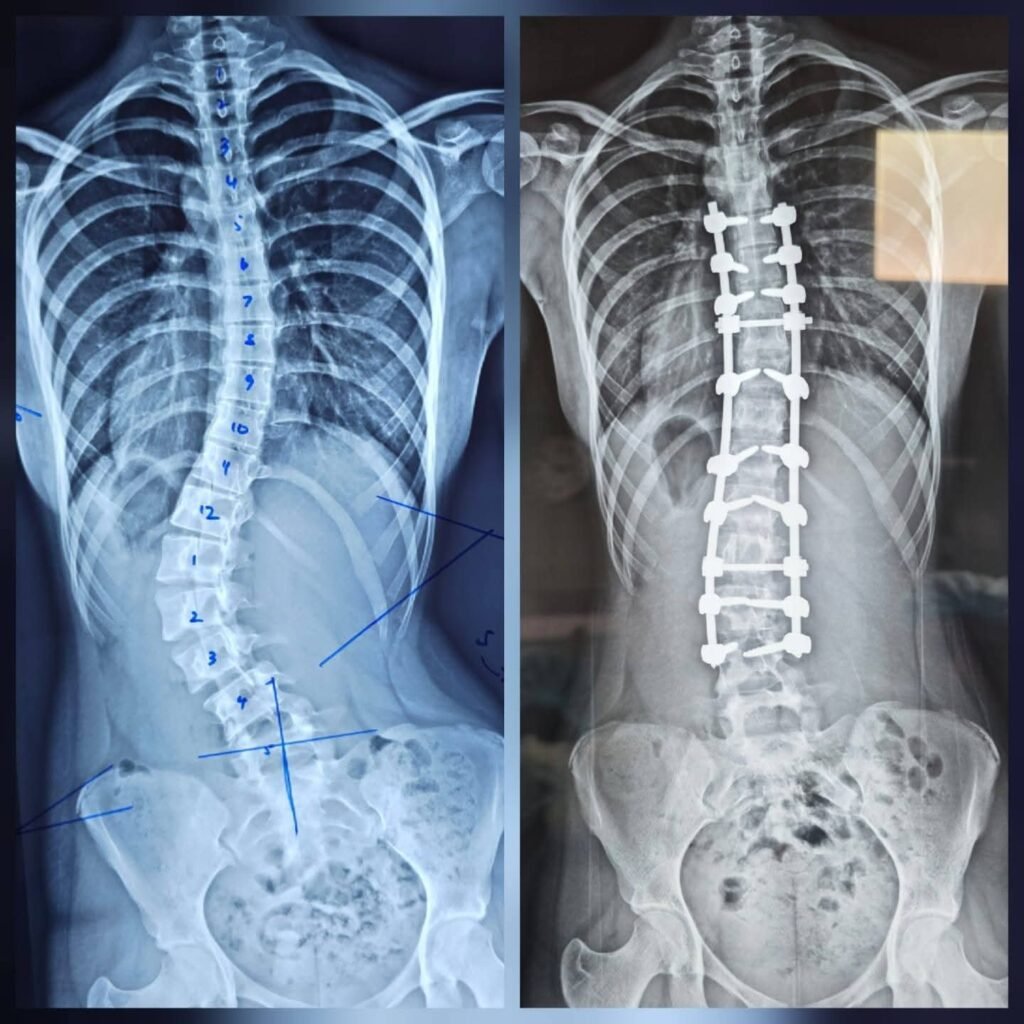

புத்தளம் தள வைத்தியசாலையில் முதன்முறையாக முள்ளந்தண்டு நேராக்கல் (Scoliosis Correction) சத்திரசிகிச்சை வெற்றிகரமாக மேற்கொள்ளப்பட்டுள்ளது.

கொழும்பு, கண்டி, யாழ்ப்பாணம், பதுளை மற்றும் இரத்தினபுரி போன்ற சில முக்கிய வைத்தியசாலைகளில் மட்டுமே இதுவரை மேற்கொள்ளப்பட்டு வந்த இவ்வகையான சத்திரசிகிச்சை, தற்போது புத்தளம் தள வைத்தியசாலையிலும் முதன்முறையாக நடைபெற்றுள்ளது என்பது குறிப்பிடத்தக்கதாகும்.

கடந்த சில மாதங்களாக முள்ளந்தண்டு தொடர்பான சத்திரசிகிச்சைகள் இவ்வைத்தியசாலையில் நடைபெற்று வந்தாலும், முள்ளந்தண்டு நேராக்கல் (Scoliosis Correction) சத்திரசிகிச்சை மேற்கொள்ளப்பட்ட முதலாவது சந்தர்ப்பமாக இது அமைந்துள்ளது.

என்பு முறிவு விசேட வைத்திய நிபுணர் டாக்டர் ஷெஸார் ஹமீத் தலைமையில் இந்த சத்திரசிகிச்சை மேற்கொள்ளப்பட்டது. இதற்காக கொழும்பு தேசிய வைத்தியசாலையைச் சேர்ந்த சிரேஷ்ட என்பு முறிவு விசேட வைத்திய நிபுணர் டாக்டர் உதை டி சில்வா மற்றும் லேடி ரிஜ்வே வைத்தியசாலையின் டாக்டர் நிர்மல் மாரசிங்ஹ ஆகியோரும் கலந்து கொண்டு மருத்துவ உதவி வழங்கினர்.

சுமார் 40 லட்சம் ரூபாவிற்கும் அதிகம் செலவாகும் இந்த சத்திரசிகிச்சை முற்றிலும் இலவசமாக மேற்கொள்ளப்பட்டுள்ளதாகவும் தெரிவிக்கப்படுகிறது.

இலங்கையில் உள்ள தள வைத்தியசாலைகளில் இதுவரை இவ்வகையான முள்ளந்தண்டு நேராக்கல் சத்திரசிகிச்சை மேற்கொள்ளப்படாத நிலையில், புத்தளம் தள வைத்தியசாலையில் இது வெற்றிகரமாக மேற்கொள்ளப்பட்டிருப்பது முக்கியமான மருத்துவ முன்னேற்றமாக கருதப்படுகிறது.